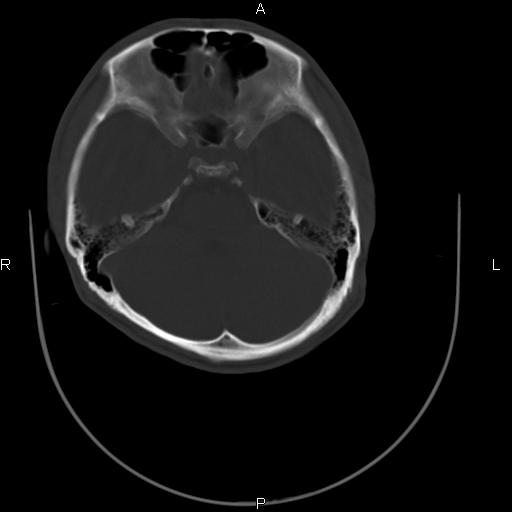

标题: CT27115:大家看一看,这孩子的颅骨表现?

两名中学生打架,脑质内未见异常,未上传。

颅骨骨质未见异常。

颅骨未见骨折征象。

两例——颅骨结构正常,未见明显骨折征象。